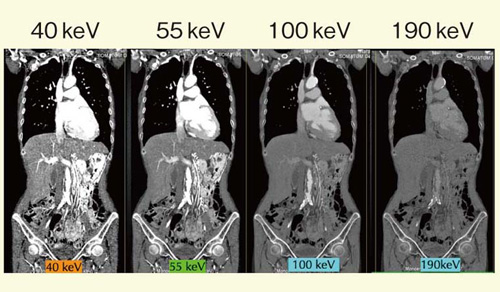

2)Monoenergetic image

monoenergetic image(仮想単色エネルギー画像)は,実効エネルギー換算が可能な画像再構成である(図7)。monoenergetic imageでは実効エネルギーをそろえることができるので,異なる装置間(またはDSCT同士でも)でのCT画像の比較が可能になる。

図7 monoenergetic image